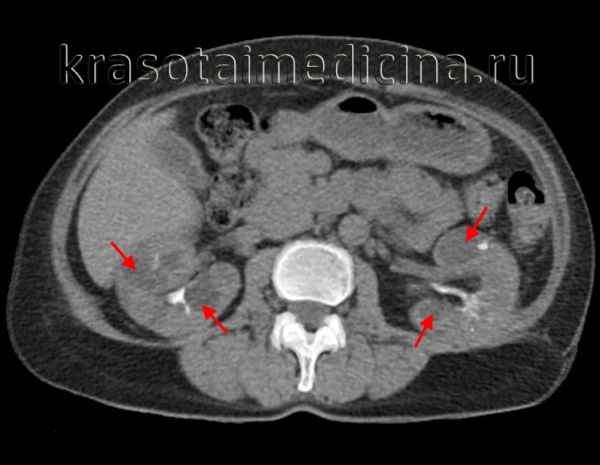

Диагностике помогают данные КТ и МРТ почек и печени и экскреторной урографии.

При МРТ собирательные трубочки расширены в виде веретенообразных, радиально расположенных кист, но решающего значения при постановке диагноза эти данные не имеют. В кисты превращены от 10 до 90% собирательных трубочек — в зависимости от тяжести и возраста начала заболевания. При биопсии печени находят разрастание желчных протоков, портальный и перипортальный фиброз.

Диагностика аутосомно-рецессивного поликистоза почек. Пальпируемое двустороннее объемное образования в боковых отделах живота у грудного ребенка с гипоплазией легких, маловодием и артериальной гипертонией в отсутствие поликистоза почек у родителей позволяет диагностировать болезнь. При УЗИ почки обычно резко увеличены и равномерно повышена их эхогенность со стертостью границы между корковым и мозговым веществом. Диагноз подтверждают также клинические и лабораторные признаки фиброза печени, патологические изменения желчных протоков в биоптате печени, наличие поликистоза почек у сиблингов или близкое родство родителей. Аутосомно-рецессивный поликистоз почек следует отличать от увеличения почек при поликистозной дисплазии, гидронефроза, опухоли Вильмса и двустороннем тромбозе почечных вен. В семьях хотя бы с одним больным ребенком возможна пренатальная диагностика с помощью анализа генетического сцепления и использования информативных маркеров.